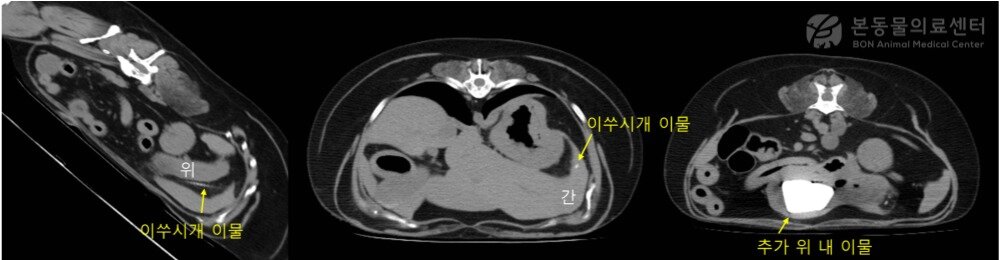

본문 이미지 - CT 검사 결과 발견된 이쑤시개 등 이물(본동물의료센터 제공) ⓒ 뉴스1

CT 검사 결과 발견된 이쑤시개 등 이물(본동물의료센터 제공) ⓒ 뉴스1